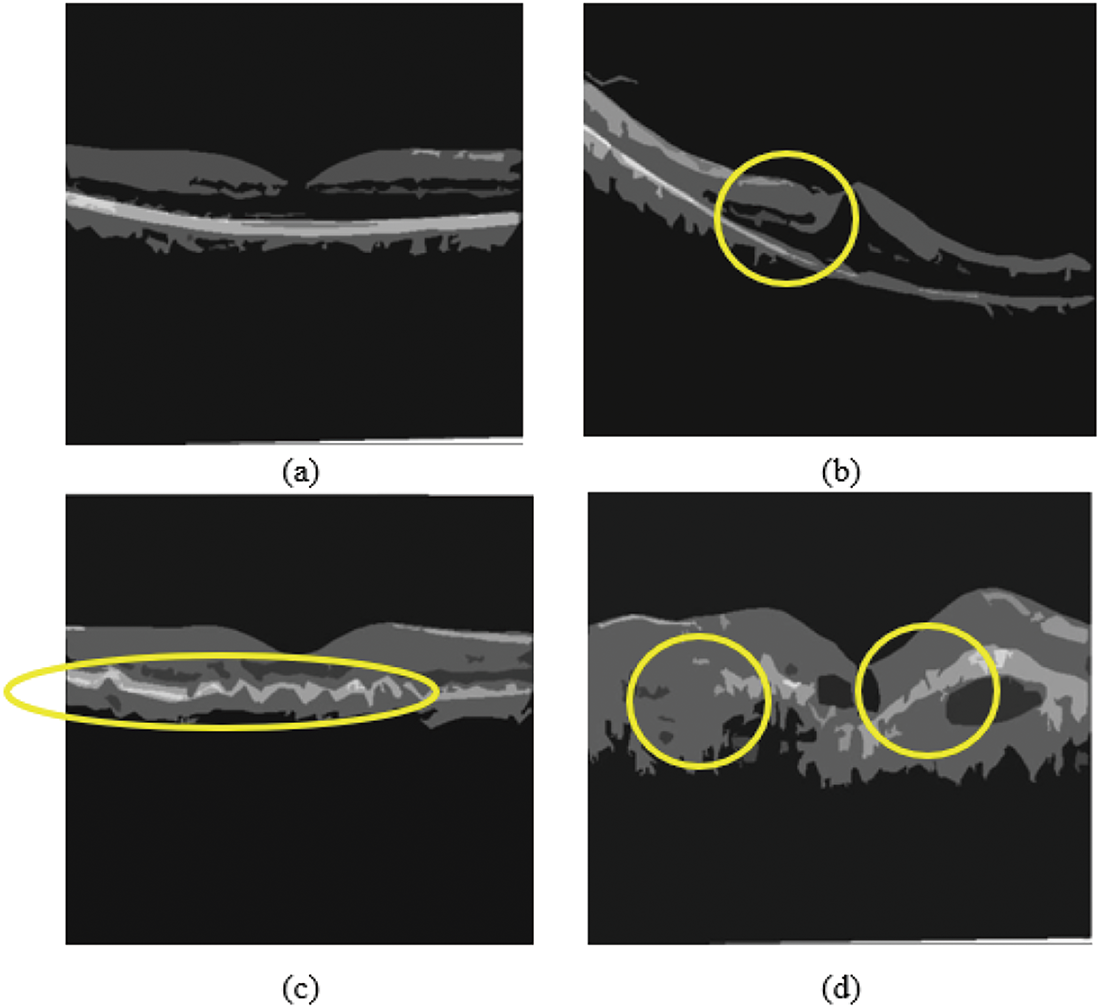

As shown in Fig. 4, the preprocessed technique increases the fundus image segmentation outcome. Compared with existing algorithms, the Contrast Limited Adaptive Histogram Equalization (CLAHE), technique improves the contrast between images. It increases vascular structures and removes the structure of non-vascular pixels. Moreover, when the image contrast is improved, further enhanced image stretching is not essential; thus, distortion of the blood vessels is avoided.

Figure 4: Preprocessed OCT image